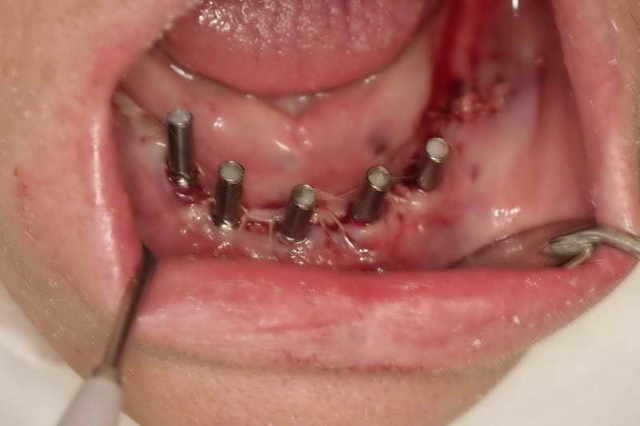

Bon, ça y est, je suis dépucelé du complet sur pilotis avec MCI.

ça s'est bien passé. J'ai posé 5 implants mandibulaires (4 de 4x13 et 1 4x11) et 1 implant maxillaire de 3x10.

La patiente est ravie, elle n'a pas mal (toute juste un peu gonflée). J'ai bien évité de léser les mentonniers ;-). J'ai pu solidariser la prothèse sur 4 implants. Le tube provisoire central était mal centré, la vis risquait de trop forcer, j'ai préféré rester ancré sur les 4 implants distaux.

Le premier résultat est conforme à mes simulations (sous facilitate = simplant par astra).

Tubes ealwqq - Eugenol